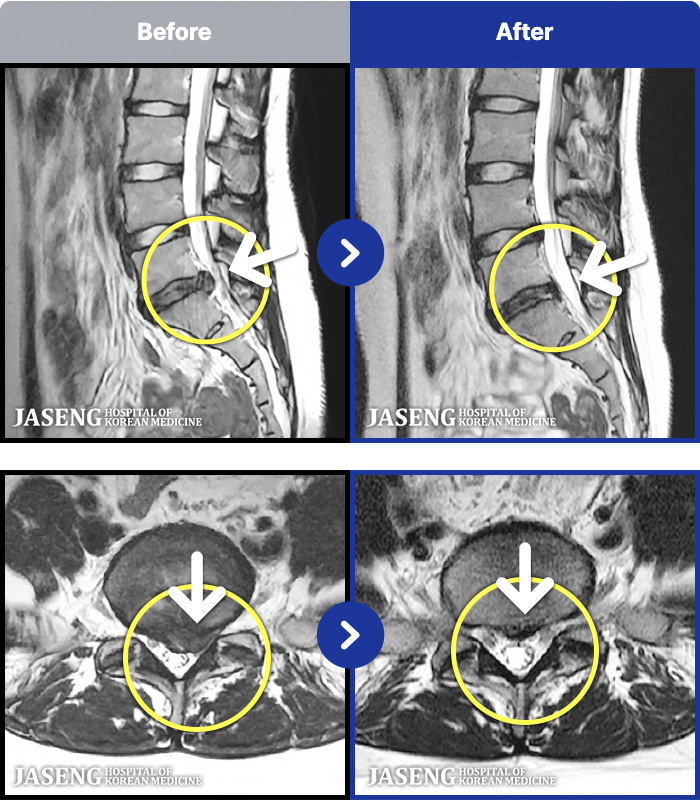

191 MRI ũ ʸ Ȯϼ.